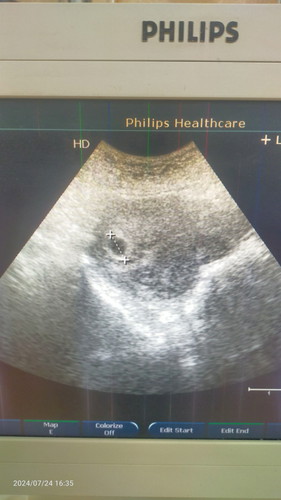

Sedih & down sgt².. ari ni ada spotting.. direct er.. doc scan hny nmpk kantung kosong.. refer pac.. pn still hny nmpk kantung kosong.. tp doc ckp.. kantung kecik sgt utk 6w6d.. tak blh pastikn lgi.. review bln dpn.. sgt² bharap smoga masi ada lgi permata ibu..

berapa size kantung sis? semoga dipermudahkan urusan sis dan baby ❤️

1.75cm jak sis